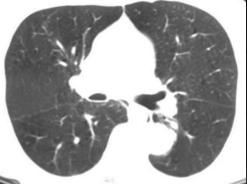

Mega oesophage : image radiologique

TDM fenetre parenchymateuse en coupe axiale |

chaussette . Image TDM en fenetre parenchymateuse pulmonaire

,se donne des images si net de oesophage en coupe axiale ,

sagitale et de frontale ( voie image )